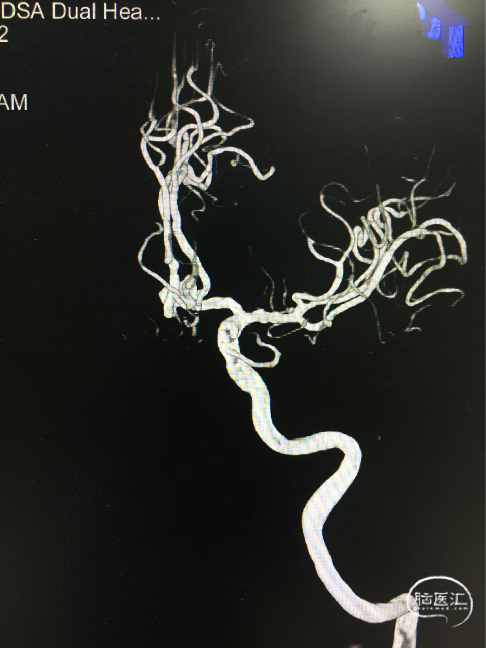

术前DSA 3D:左颈内动脉正侧位及工作位,前交通动脉瘤,约4×8mm,颈宽约6.5mm,形态宽颈、分叶。前交通动脉及大脑前动脉A1、A2直径约2mm。

术前DSA:LICA正侧位及工作角度造影显示前交通动脉瘤

术前DSA:RCCA正侧位造影